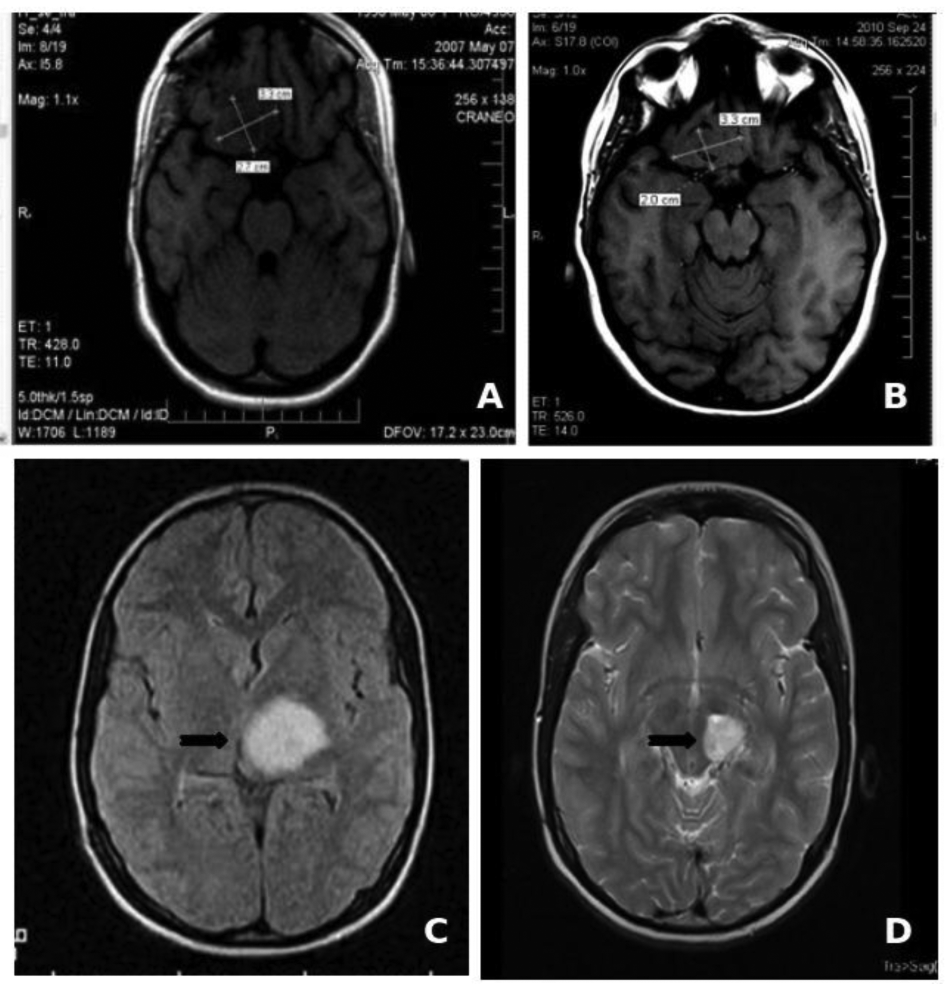

The low toxicity profile shown by Nimotuzumab has allowed its use in prolonged treatments, lasting several months, and even years in many cases. About two thirds of the 600 patients that have been treated in Cuba since 2002 have received more than six doses of the antibody (200 mg for adult, 150 mg for children), including about 50 patients that have been treated with more than 30, bi-weekly doses during more than one year [50]. In particular, two children with brain stem glioma tumors have received more than 100 doses of Nimotuzumab, continuously for more than three years, without showing adverse effects (Figure 1). It is worth noting that the frequency of adverse events (limited to grade 1 or 2) observed in these patients did not increase with drug exposure. From this clinical experience we have obtained important evidences on the impact of chronic treatment in disease stabilization and increase of overall survival in advanced cancer patients.

We are grateful to Ricardo Cabanas (Juan Manuel Márquez Hospital, Havana), as well as Patricia Piedra and Gisselle Sáurez (Center of Molecular Immunology) for providing the MRI images and data on clinical studies in pedriatic glioma patients.